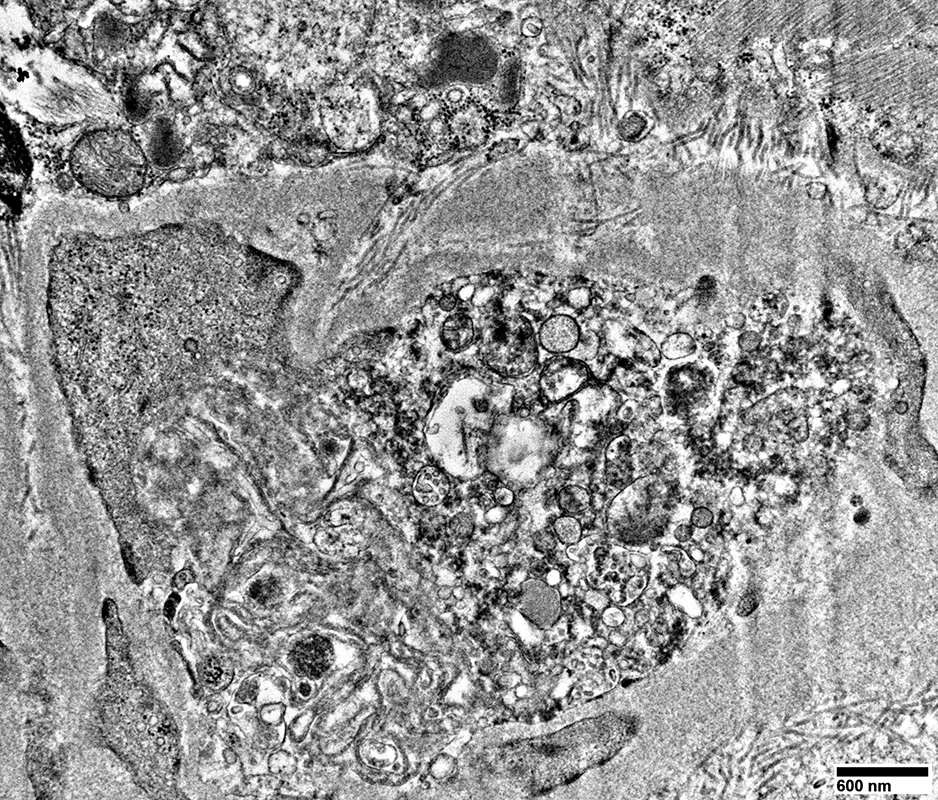

Large cells near vessels with cytoplasm nearly replaced by

Mitochondrial proliferation & enlargement

Lipid droplets

From: R Schmidt